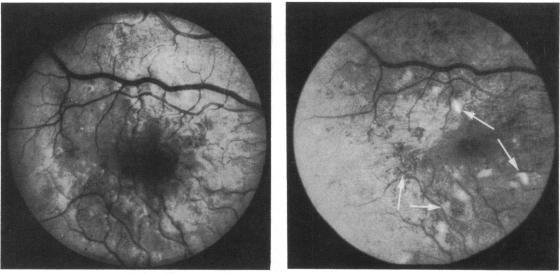

Continuous subcutaneous insulin infusion (CSII) does not prevent progression of proliferative and preproliferative retinopathy.

Br J Ophthalmol. 1982 Dec;66(12):762-6. doi: 10.1136/bjo.66.12.762.